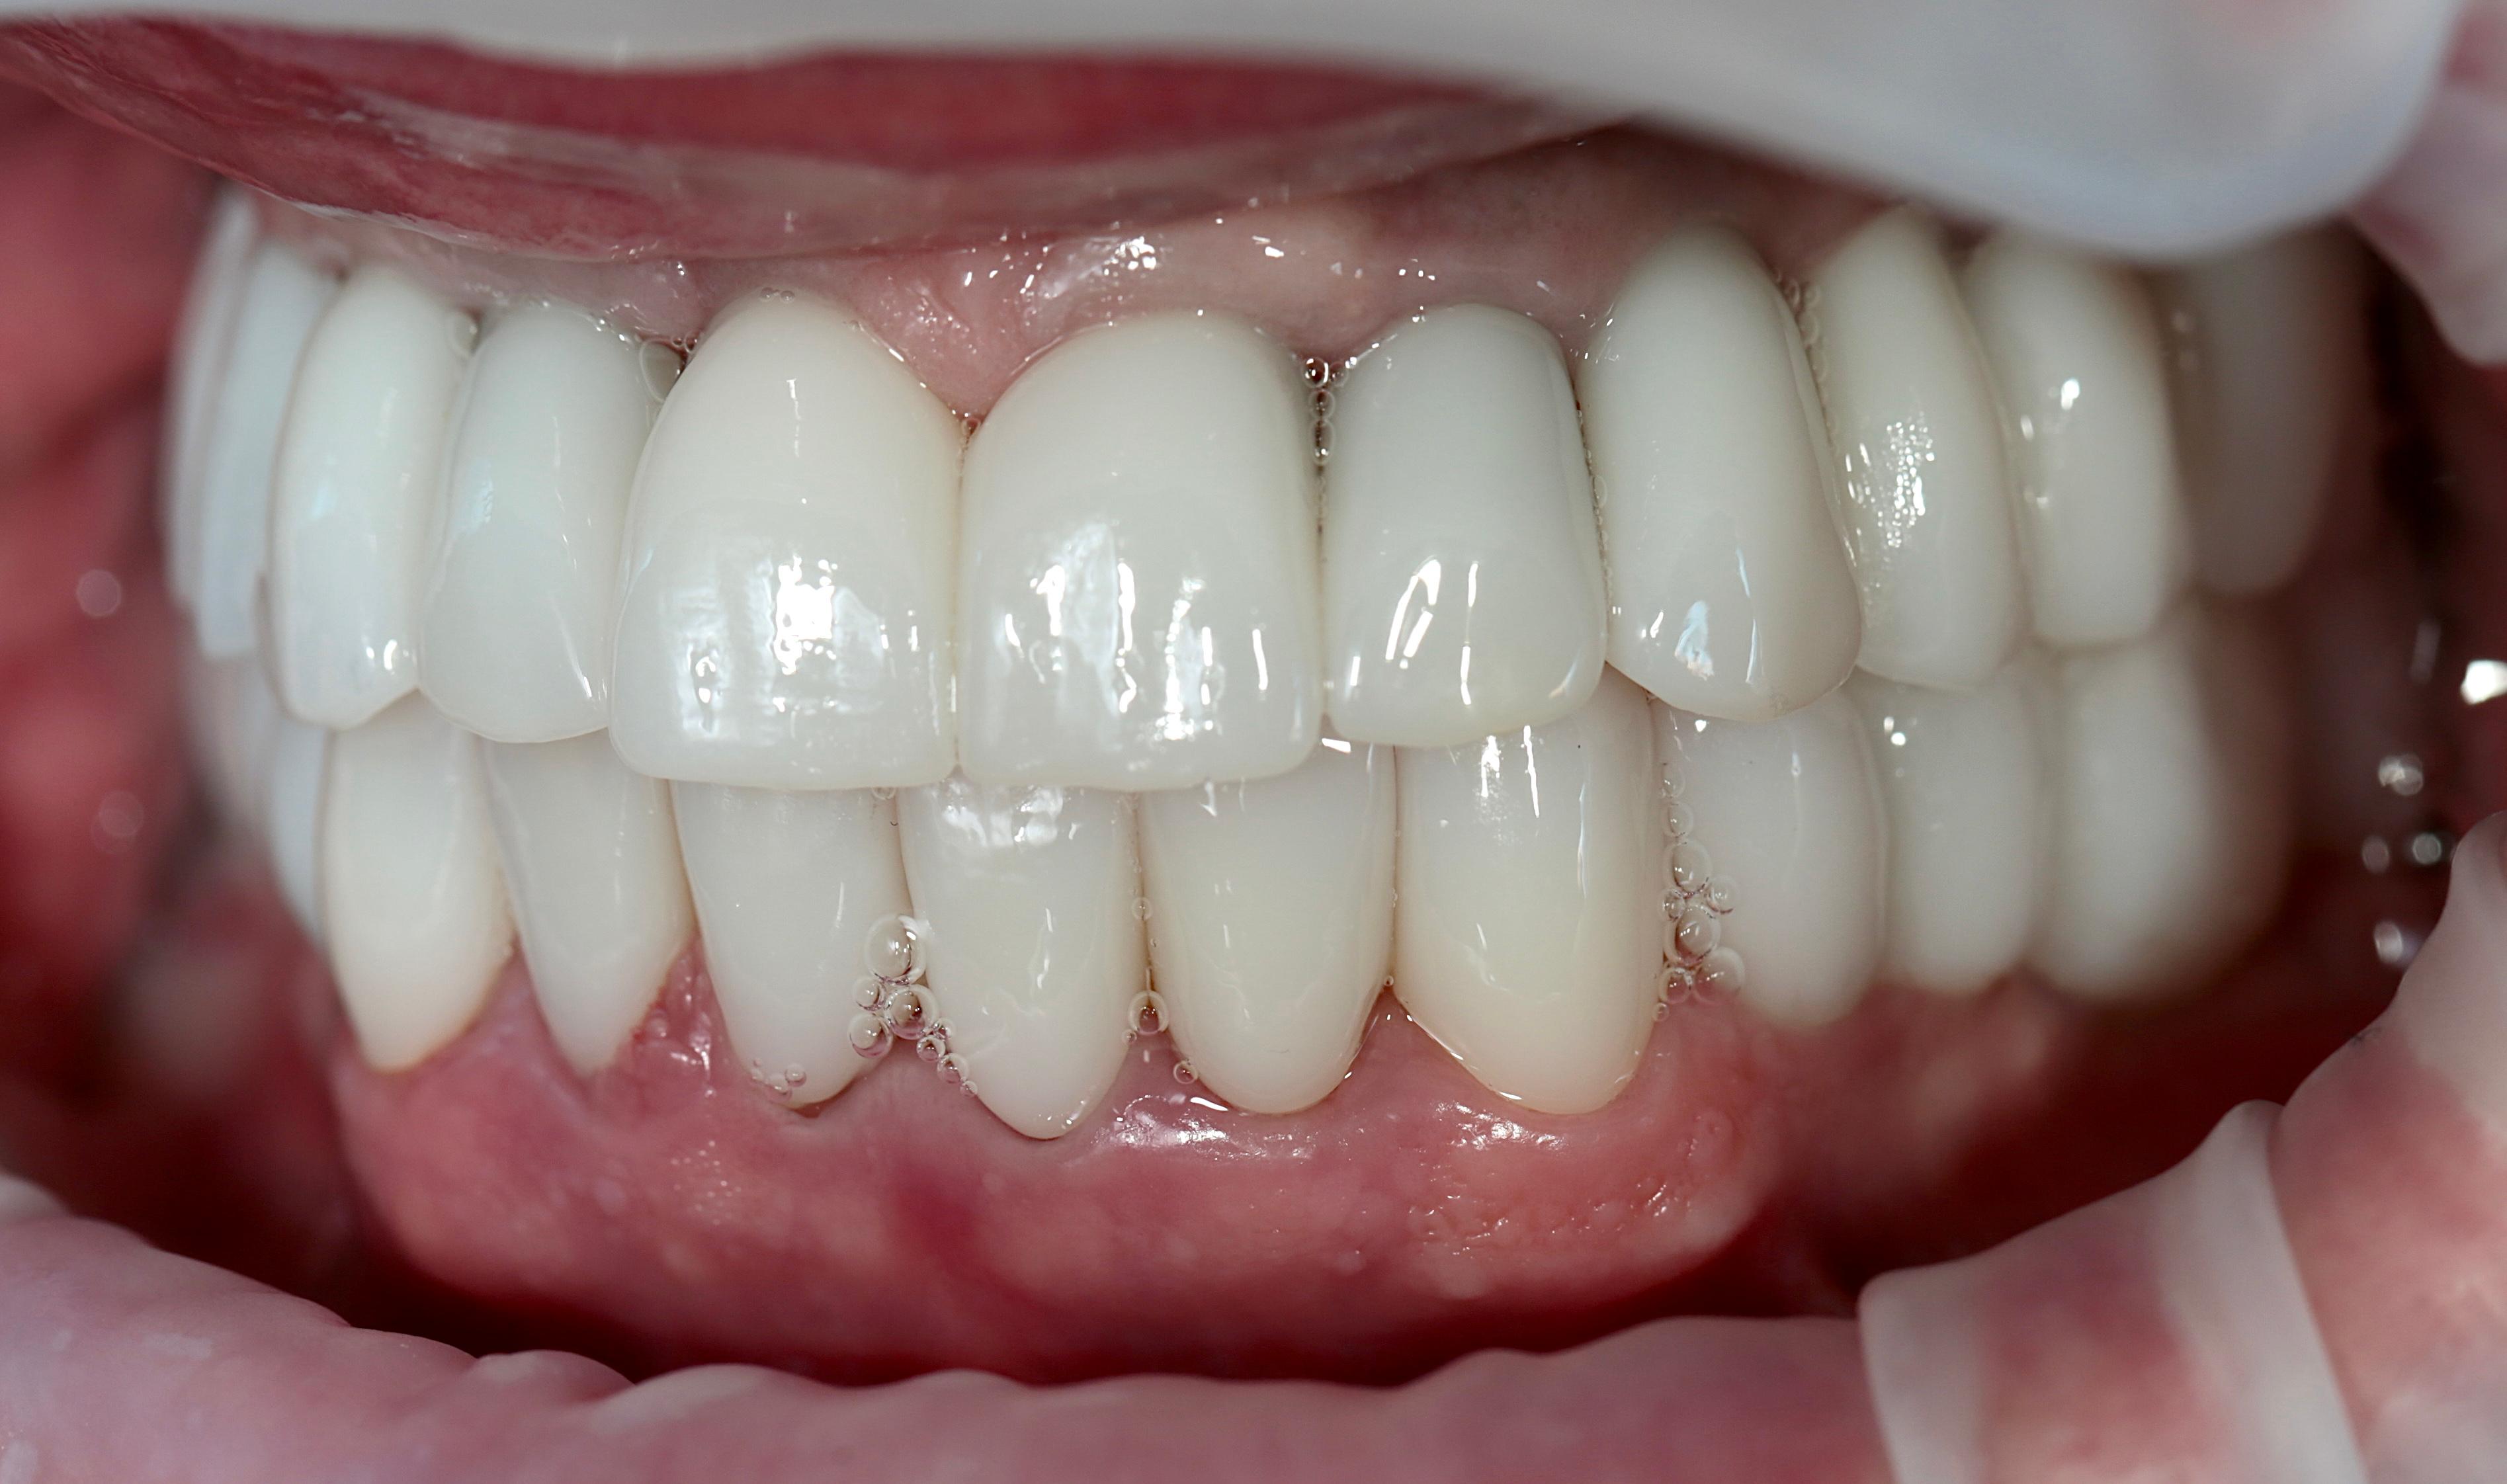

Циркониевые коронки на имплантах

На временных коронка проверена высота прикуса и окклюзия.

Установлены коронки из оксида циркония с опорой на импланты и керамические виниры на нижних фронтальных зубах.